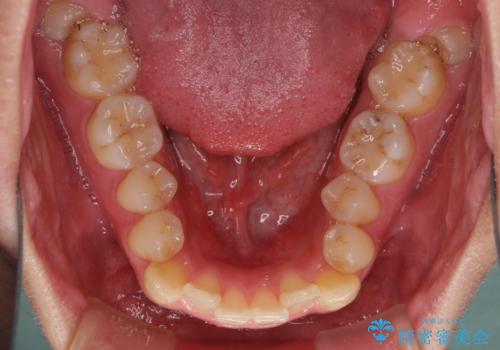

狭い歯列と前歯のデコボコ インビザラインによる矯正治療

- 上下前歯のデコボコを気にして来院された患者様です。

インビザラインによる上下歯列の拡大と、IPR(歯と歯の間を削る)にるスペースの獲得により、前歯のデコボコと狭い歯列を改善することとしました。

比較的軽度な歯列不正であったため、治療期間はそれほど長くはならないと予想されました。

また、仕上がりの歯列にも若干の叢生が残ってしまいました。